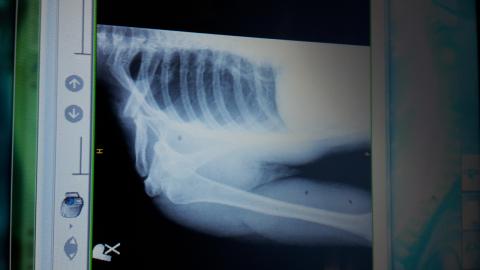

chcel by som sa spytat ci sa da zoperovat zle zrastena zlomenina claviculy? Som uz vyse 2mesiacov po zlomenine a mi to pomerne vadi a k tomu mi trpnu prsty da sa po takej dlhsej dobe operovat znova lamat a drotovat?

Dobrý den, i taková možnost tu existuje, bohužel její výsledky nemusí být dobré, není to jako u čerstvé zlomeniny. Divím se, že takovou zlomeninu vám neoperovali a nechali jen srůst. Zkusila bych ještě rehabilitace na uvolnění pohybů a vitamin B k posílení regenerace nervu.